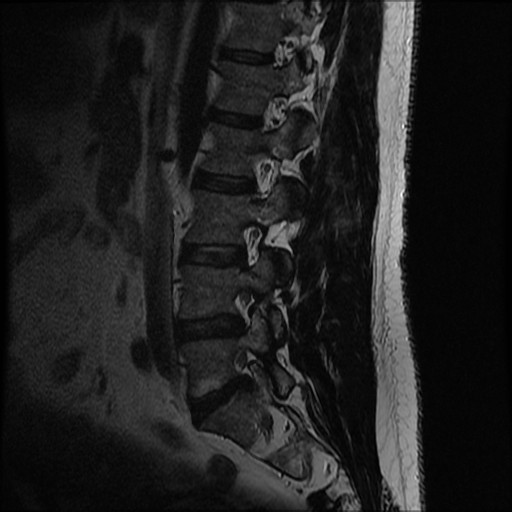

MRI

T2 Sagittal - myelogram

T1 Axial - see nerve root against white fat

MRI changes

1. Central root clumping

2. Empty sac appearance

3. Soft tissue mass in subarachnoid space